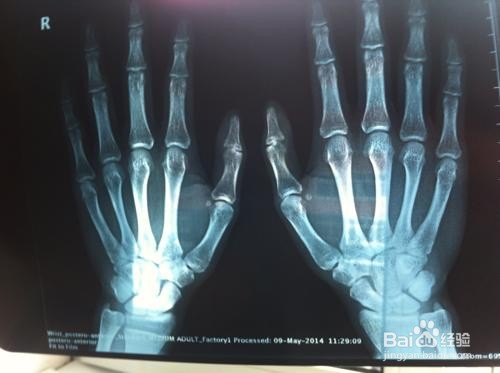

1、骨龄是骨骼年龄的简称,借助于骨骼在X光摄像中的特定图像来确定。在了解人的骨龄情况时,通常要拍摄人左手手腕部的X光片,医生通过X光片观察左手掌指骨、腕骨及桡尺骨下端的骨化中心的发育程度,来确定骨龄。

2、测定骨龄的方法有简单计数法、图谱法、评分法和计算机骨龄评分系统等,最常用的是G-P图谱法和TW2(TW3)评分法;预测成年身高包括B-P法、RWT法、TW2法等。